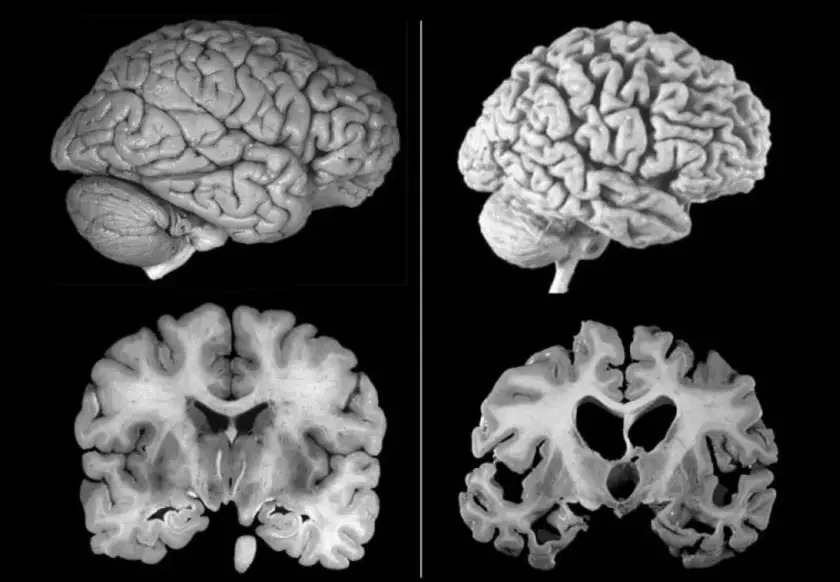

U mozhu pacyjentaŭ byli znojdzieny białki virusa prostaha hierpiesu pieršaha typu (VPH-1) pobač z charakternymi dla zachvorvańnia skučanaściami tau-białku ŭ najbolš uraźlivych zonach mozhu.

Ekśpierymienty na łabaratornych madelach mozhu čałavieka pakazali, što virus hierpiesu moža ŭpłyvać na ŭzrovień tau-białka. Spačatku heta źjaŭlajecca achoŭnym miechanizmam, jaki źmianšaje hibiel niejronaŭ paśla virusnaj infiekcyi. Adnak ź ciaham času takaja abarona moža pryvieści da paškodžańnia mozhu.

«Naša daśledavańnie źmianiaje ŭjaŭleńnie pra tau-białok jak vyklučna škodny faktar. My pakazali, što jon moža być častkaj imunnaj abarony mozhu», — adznačyŭ kiraŭnik daśledavańnia Or Šemieš.